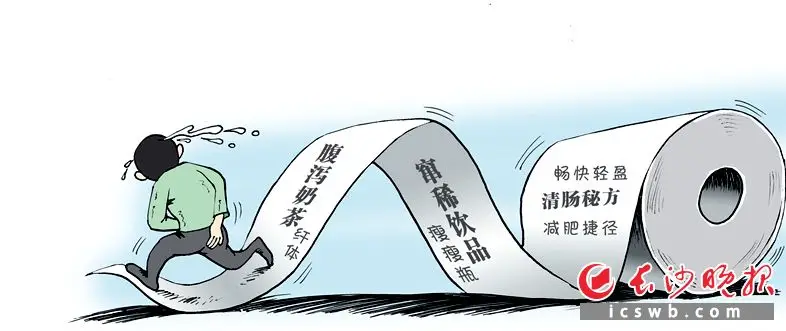

“瘦身奶茶”“腹瀉奶茶”成為網紅爆款 小心“瘦身”變“傷身”

“瘦身奶茶”“腹瀉奶茶”“竄稀飲品”成為網紅爆款瘦身,專家提醒—— 別輕信清腸秘方瘦身,小心“瘦身”變“傷身” 漫畫/餘寧山 長沙晚報全媒體記者 楊雲龍 通訊員 李澤湘 近來,“瘦身奶茶”“腹瀉奶茶”“竄稀飲品”成為網紅爆款瘦身。據說,這類主打“暢快輕盈”的飲品,飲用後能讓人迅速產生“通暢”的體驗,